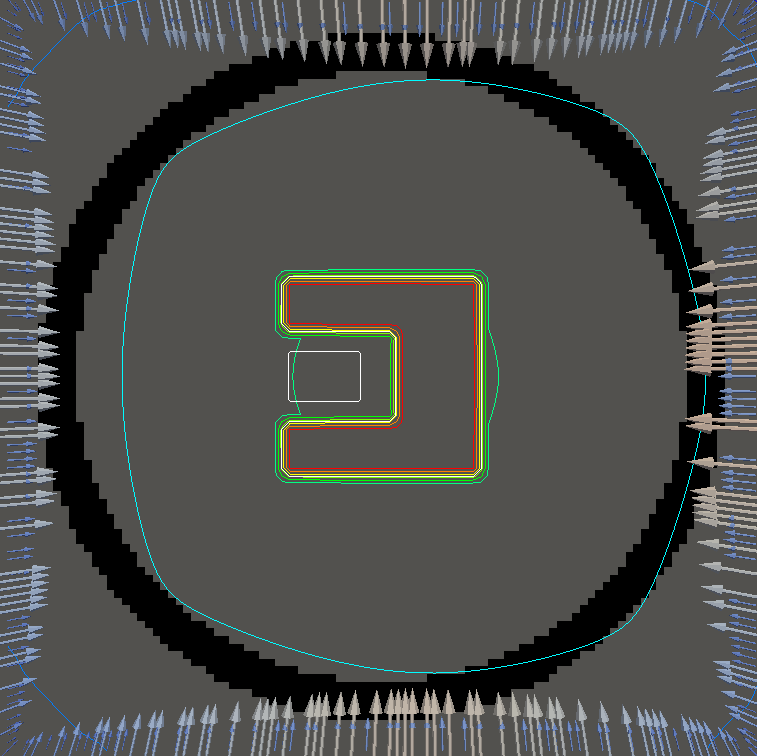

For testing, we use three tumor/risk region regions similar to those in [13]. Specifically, we define the regions in Table 3 and are shown in Figure 1; the void region is shown in black and the tumor and risk regions are traced in white. In the basic target case, seen in Figure 1(a), the tumor region is a box, as is the risk region. The second, intermediate target case, seen in Figure 1(b), involves an L-shaped tumor around a box-shaped risk region. Finally, the complex target case in Figure 1(c) involves a C-shaped tumor around a risk region.

Figure 2 shows the optimal boundary source term for both and The vectors shown on the boundary are the time-integrated values of normalized and then scaled by In Figures 2(a), 2(c), and 2(e) (corresponding to ), the isolines are spaced at intervals of the maximum of the desired dose (here, 5). In the intermediate and tracking cases, we see that relatively low dose levels are attained, primarily due to the high penalty to any dose deposited in the risk region. In Figures 2(b), 2(d), and 2(f)(corresponding to ), the isolines are spaced at intervals of of cells killed. Here a high proportion of the tumor cells are killed (in each case ) while in the Intermediate and Basic cases, the tumor has at least survival; in the Complex case, the risk region has survival.